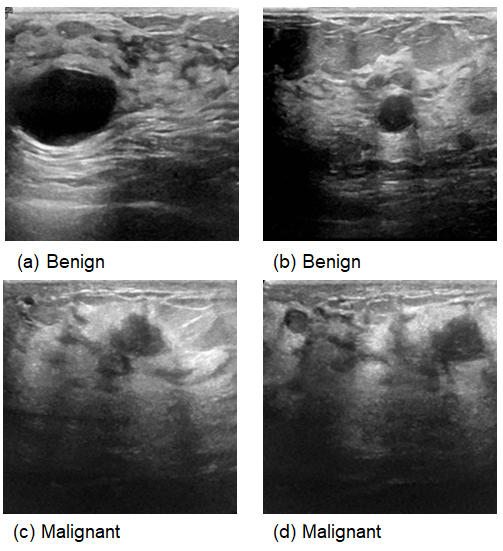

This comprehensive approach of utilizing datasets from multiple imaging modalities shown in Figure 1, Figure 2, Figure 3 and Figure 4 and summarized in Table 1, including mammography, ultrasound, MRI, and histopathological images, ensures robust model validation and enhances the system’s capacity to accurately classify benign and malignant findings. By leveraging these diverse datasets, we aim to develop a more generalizable and effective breast cancer classification system.

Figure 2. Samples from the magnetic resonance imaging (MRI) dataset.